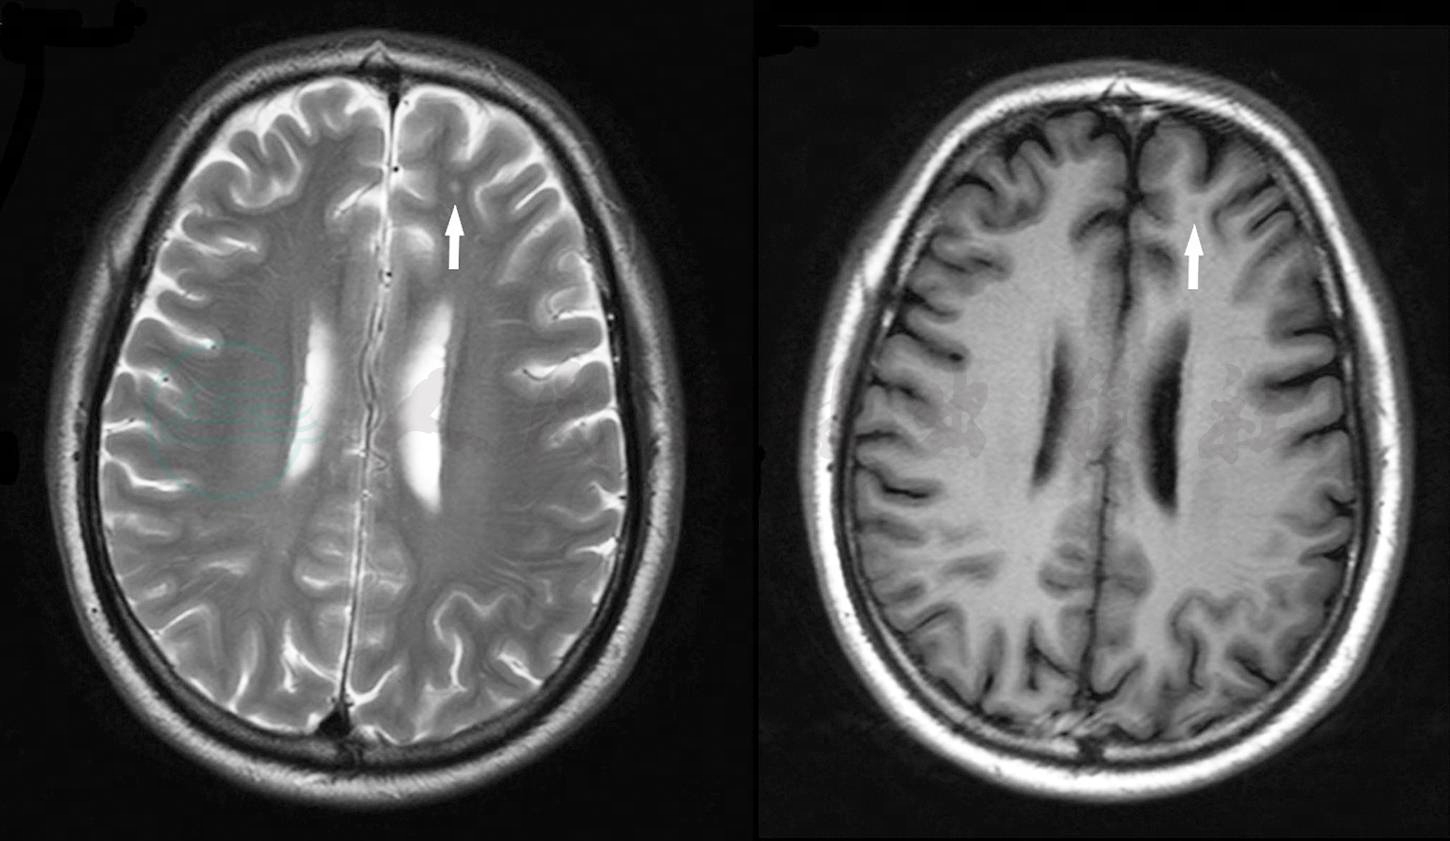

诊疗过程:入院第3日,查脑电图示“两半球基本波率为9~10Hz中-高幅α节律,以顶枕区为主,双侧基本对称,调节波幅较差,各导联可见较多中-高幅θ波及θ活动,混杂少量δ波活动,部分慢波呈阵发性出现,期间混杂较多低幅快波。视反应:α节律抑制完全。过度换气:波率变慢,慢波增多,可见少量散在性尖波发放,波及各导联。过度换气后恢复较差,印象:①脑电图:轻度异常;②脑电地形图:轻度异常”。头颅MRI示“头颅MRI平扫示左侧额叶皮层下小斑片状稍长T2异常信号灶,影像提示缺血灶”(图1)。

图1 左额叶皮层下缺血灶